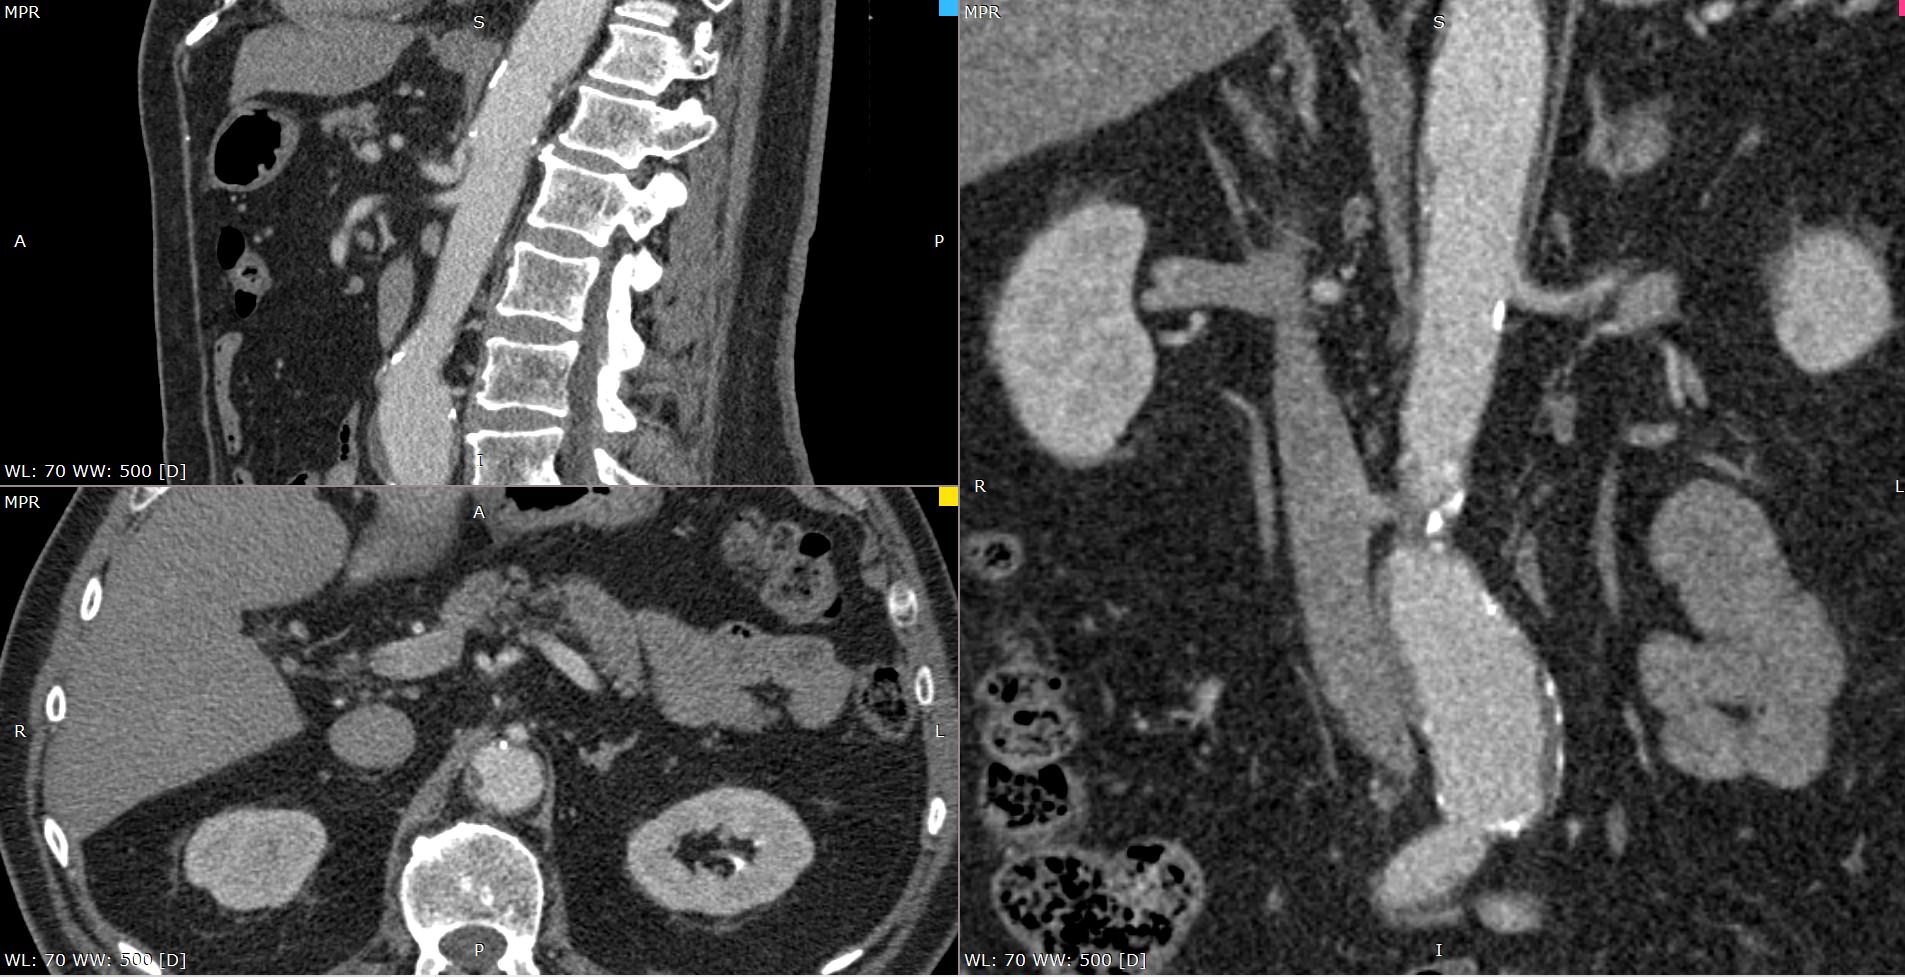

При возникновении подозрения на стеноз чревного ствола за счет экстравазальной компрессии при синдроме Данбара исследование проводится с функциональными пробами, на вдохе и на выдохе для уточнения зависимости степени сужения от фазы дыхания. При выполнении функциональных проб также возможно определить сдавление правой почечной артерии или левой почечной вены.

Мультиспиральная компьютерная томография с внутривенным болюсным контрастированием является быстрым, безопасным и неинвазивным (то есть не требующий вмешательства в организм пациента) способом диагностики патологии чревного ствола. Метод основан на использовании ионизирующего излучения и способности тканей поглощать рентгеновские лучи.

В диагностических центрах «Доступная медицина» КТ чревного ствола выполняется на современных мультиспиральных компьютерных томографах экспертного класса TOSHIBA AQUILION. Аппараты послойно сканируют исследуемую область с шагом от 0,5 мм, при этом для улучшения визуализации сосудистого русла в вену пациента вводится йодсодержащий контрастный препарат.

Контраст хорошо поглощает рентгеновские лучи, что обеспечивает высокую контрастность изображений брюшной аорты и висцеральных ветвей на снимках. С помощью инновационных цифровых приложений данные, полученные при сканировании, реконструируются в трехмерные изображения сосудистой системы. Методика обеспечивает точную и достоверную диагностику стенозов чревного ствола, при этом современные технологии, применяемые при сканировании, сводят к минимуму лучевую нагрузку на пациента.

На снимках мультиспиральной компьютерной томографии с контрастированием хорошо визуализируется брюшная часть аорты, чревный ствол, брыжеечные артерии. При этом можно выявить признаки поражения висцеральных ветвей аорты, то есть сужение просвета сосудов за счет: